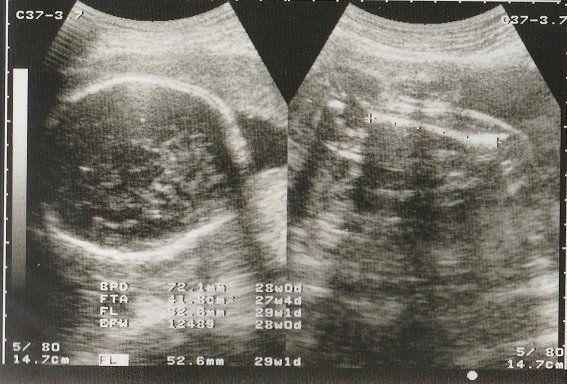

妊娠29週目のエコー写真 お母さんの体にむくみなどが出てくる時期

赤ちゃんの眼球が写っています。このころ、おなかのなかで赤ちゃんも寝たり起きたりしているそうです。

この時期になると、手足のむくみが気になるようになりました。

妊娠30週目のエコー写真 お母さんも大きくなる時期

赤ちゃんも順調に育っていますが、お母さんの体重も増え気味に…。「あまり体重が増えると管理入院ですよ」と、看護婦さんに釘を刺されました。